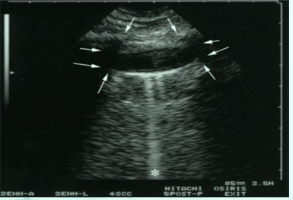

少量胸腔积液可以看到四边形征和正弦征,四边形征指胸腔积液时将胸膜

胸腔积液超声模板

胸腔积液超声图片

胸腔积液超声图片讲解

胸腔积液的超声表现图

超声测胸腔积液图解